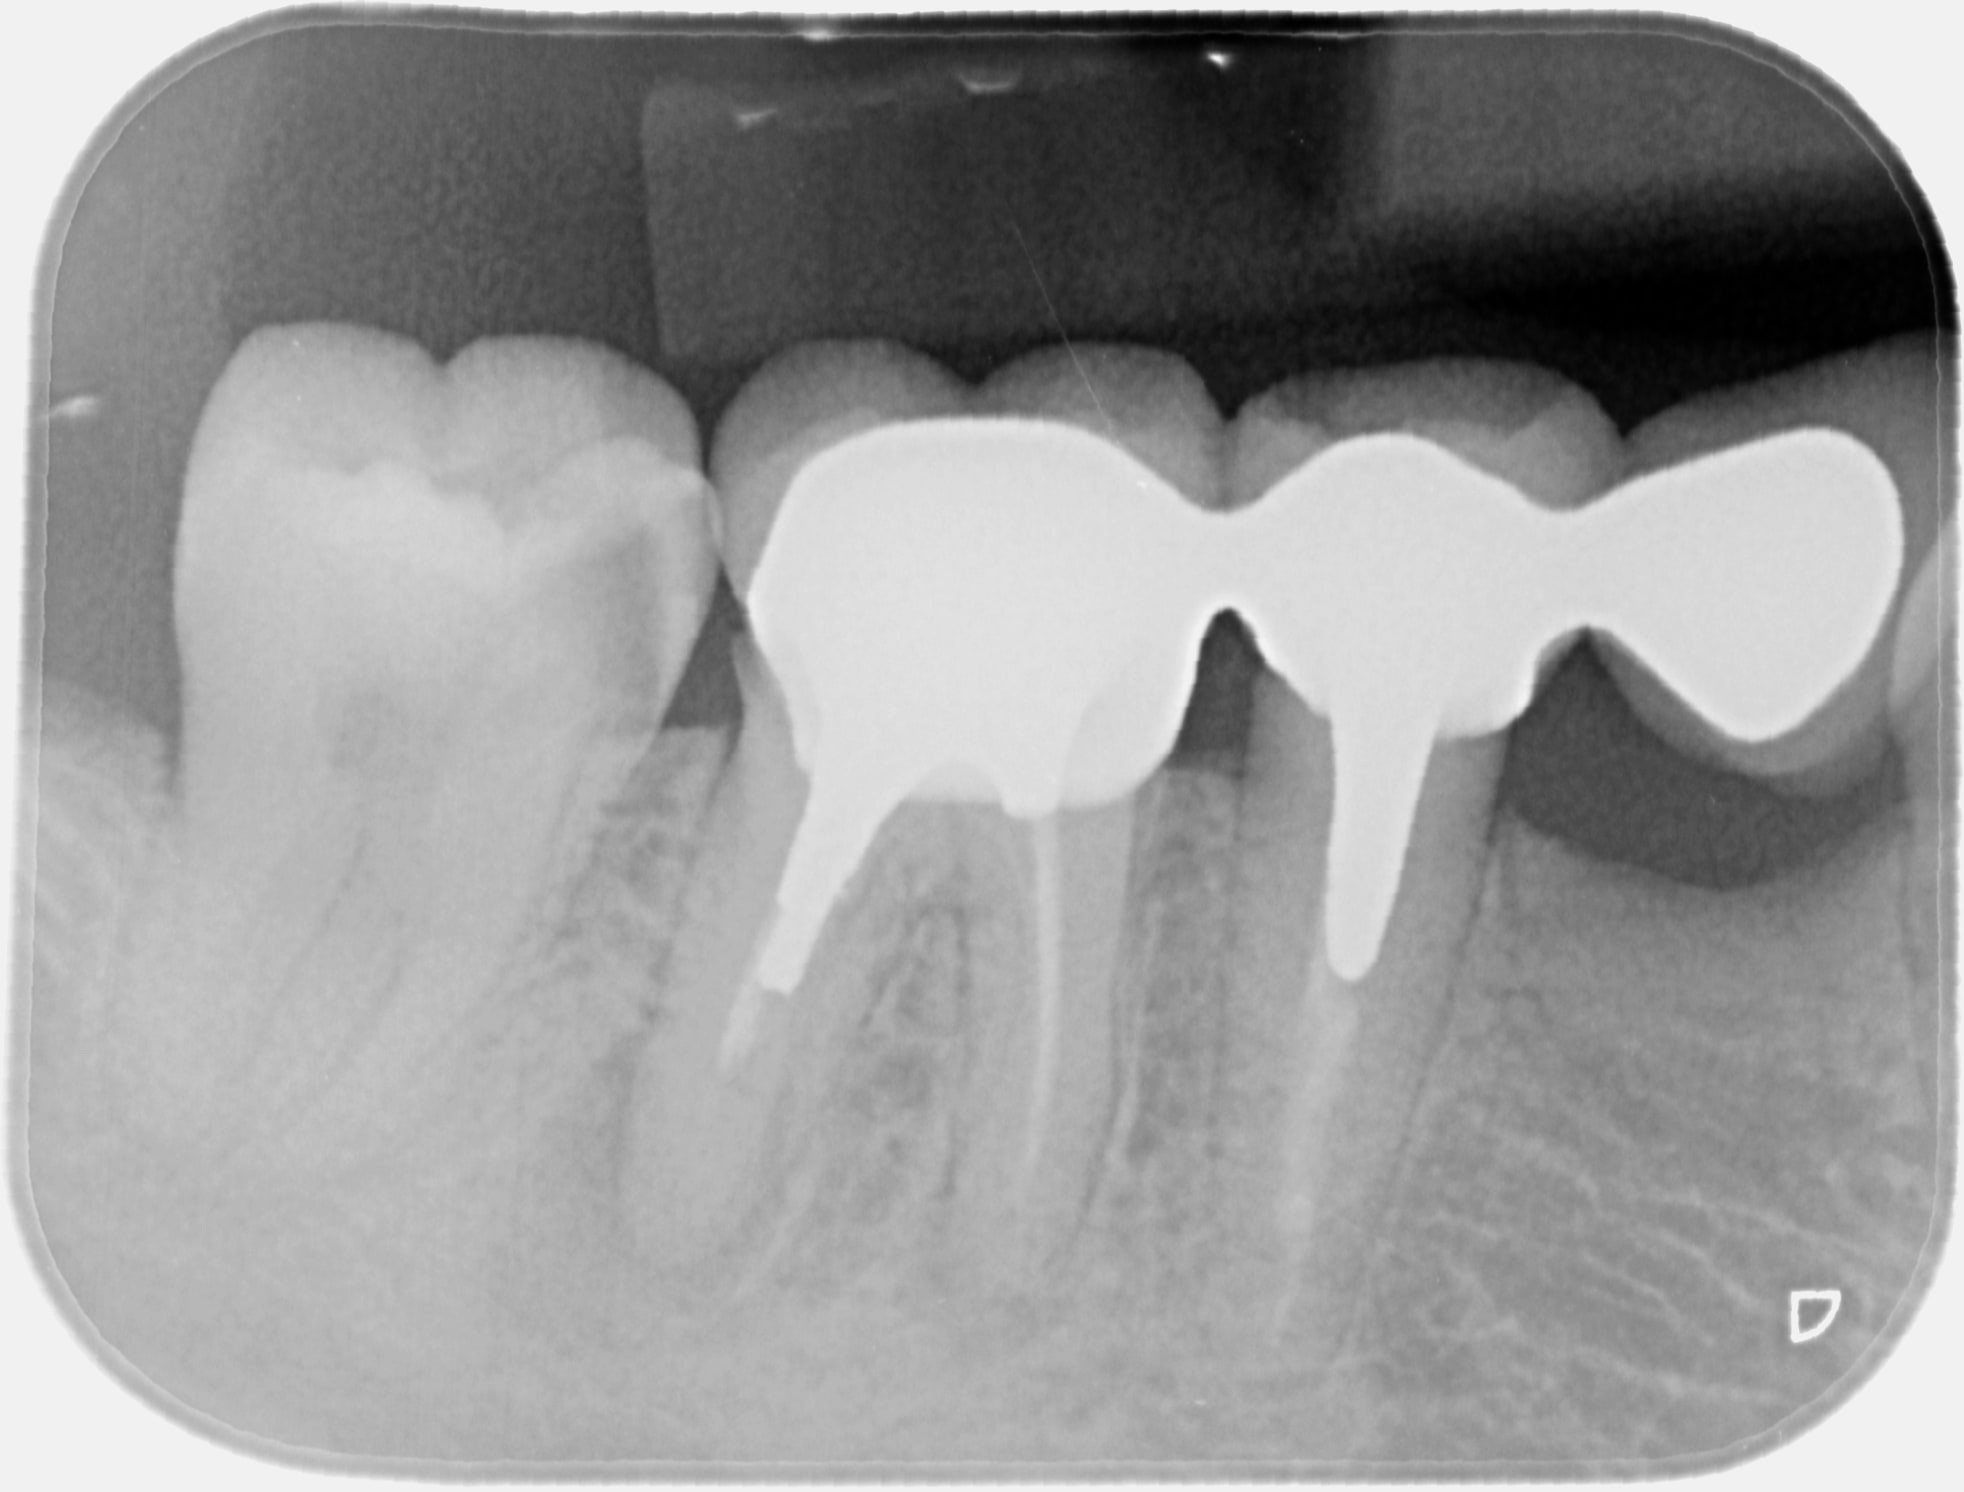

Et sinon.... patiente qui devait revenir depuis..... presque 2 ans mais comme elle se cague dessus d'aller chez son dentiste elle a reporté un 1er rdv, puis "oublié" le 2eme, puis refilé le 3eme à son minot puis... puis.... je la vois finalement lundi.

Initialement c'était pour attaquer sa 46 et le merveilleux bridge sur de merveilleuses endo qui vient dessus.

2/ comme je sais qu'une lesion apicale couve sous cette dent j'arrive Ă  la convaoncre de faire une radio et lĂ  on trouve un truc sur la 47...